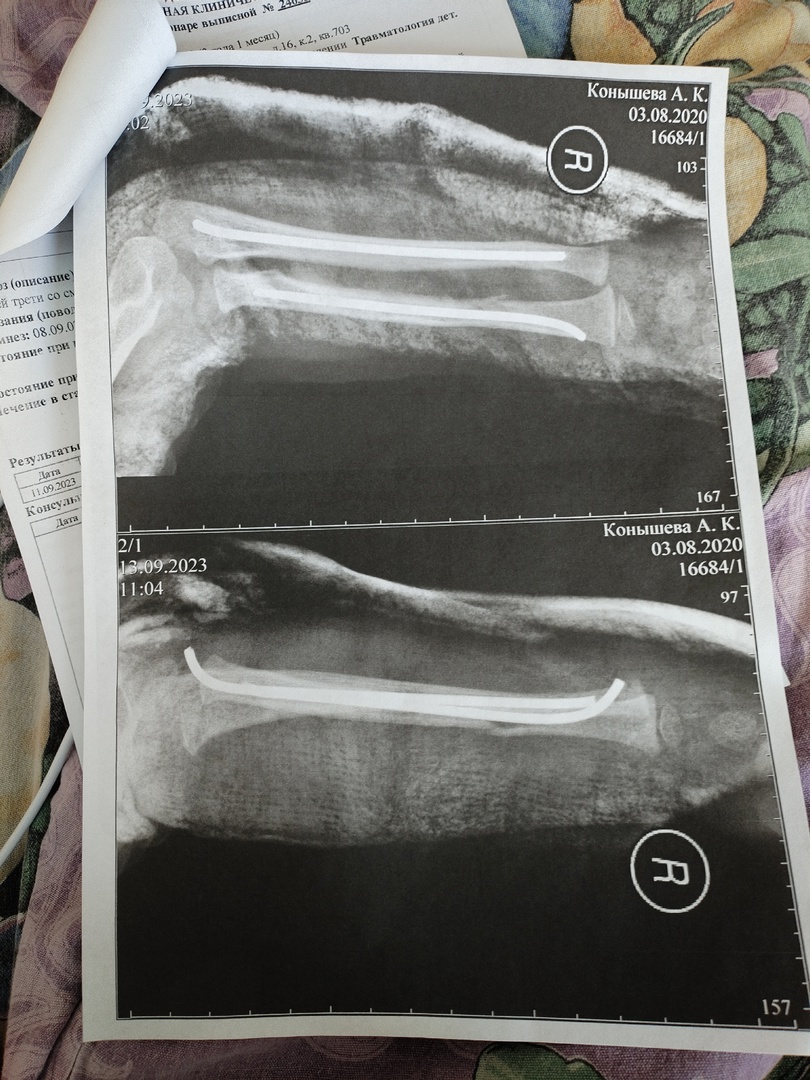

— Моя трехлетняя дочь сломала руку на вечерней прогулке. Медики диагностировали перелом лучевой и локтевой костей со смещением, была проведена операция, вставлены спицы. Теперь у дочери останутся на всю жизнь шрамы, — говорит Полина.